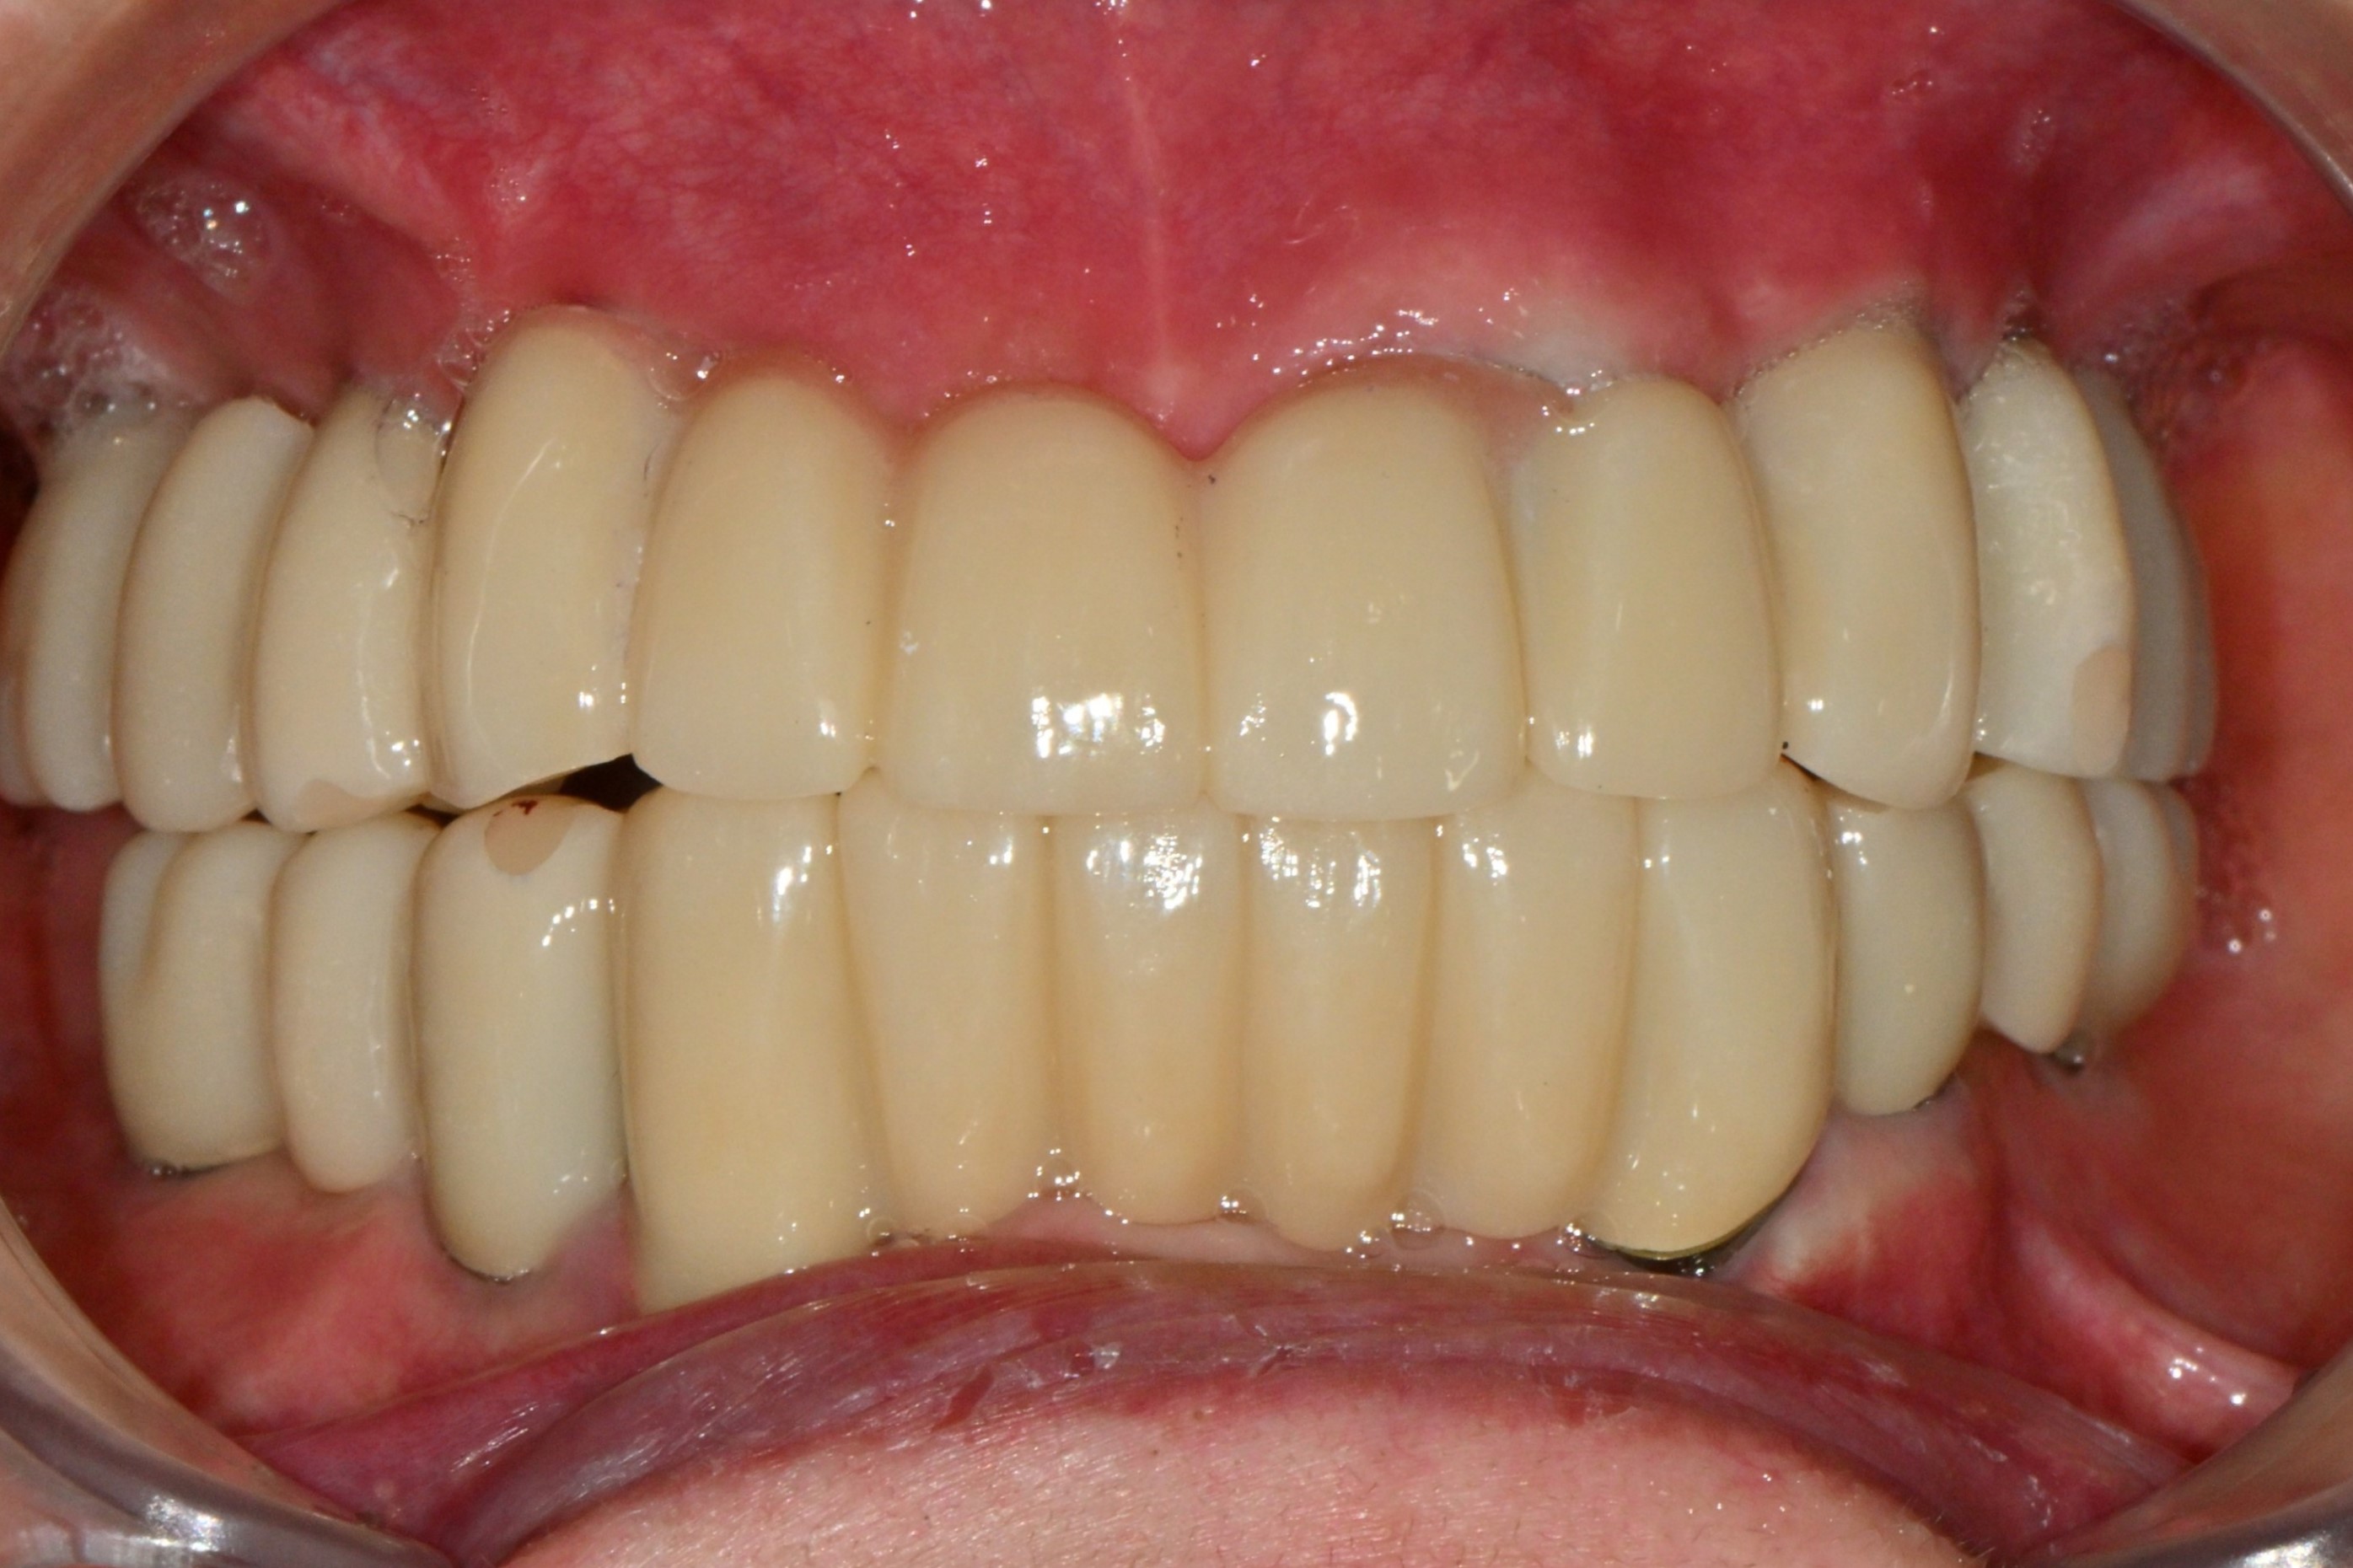

촬영일시: 2025.12.31 [ 치료기간: 2025년 06월 05일 ~2025년 12월 31일 ] ※ 365서울앞선치과의원의 모든 컬럼은 각 진료과 의료진이 직접 작성합니다. 365서울앞선치과의원 임상 케이스 게시물은 환자분께 의학적으로 정확하고 상세한 정보를 드리기 위해 각 진료과 의료진이 직접 작성하며, 모든 증례 사진은 본원 의료진이 직접 시술한 증례를 촬영한 것으로, 의료법 제23조, 제56조에 의거하며 환자분의 동의를 얻어 포스팅에 사용하였습니다. 또한 해당 케이스는 본 환자분의 치료 결과이며, 환자 상태에 따라 치료의 결과는 달라질 수 있습니다. |